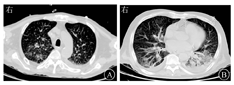

例2 患者男,68岁,既往有类风湿性关节炎及糖尿病病史。因"腹痛、腹胀2个月"于2021年5月20日收治于复旦大学附属华山医院ICU。2021年3月24日患者因腹痛、腹胀伴恶心、呕吐于外院就诊。查血常规:白细胞计数为3.28×109/L,中性粒细胞比例为0.718,淋巴细胞比例为0.147,单核细胞比例为0.094,嗜酸性粒细胞比例为0.04,血红蛋白为122 g/L,血小板计数为233×109/L。ALT为20 U/L,AST为17 U/L,总胆红素为22.0 μmol/L,白蛋白为34 g/L,肌酐为52 μmol/L。腹部CT检查示腹部部分肠管积气,少许散在小液平;肺部CT检查示两肺多发斑片影,部分伴实变。诊断为"不完全性肠梗阻,肺部感染",予禁食、胃肠减压,采用左氧氟沙星0.4 g/d静脉点滴,头孢曲松2.0 g/d静脉点滴抗感染治疗后无明显缓解。为求进一步诊治收入复旦大学附属华山医院。入院体格检查:消瘦,四肢可见瘀斑、瘀点。双肺可闻及明显湿啰音。腹膨隆,腹软,无压痛,墨菲征阴性,移动性浊音阴性,双下肢未见明显凹陷性水肿。入院后查血常规:白细胞计数为4.00×109/L,中性粒细胞比例为0.881,淋巴细胞比例为0.077,淋巴细胞绝对值为0.31×109/L,单核细胞比例为0.042,嗜酸性粒细胞比例为0.02,血红蛋白为72 g/L,血小板计数为218×109/L,CRP为9.95 mg/L,ALT为35 U/L,AST为18 U/L,总胆红素为15.7 μmol/L,白蛋白为25 g/L,球蛋白为31 g/L,肌酐为25 μmol/L。补体C3为0.585 g/L,C4为0.147g/L,类风湿因子为451 IU/mL。肺部CT检查示:双肺散在斑片影,双侧胸腔积液(图3)。查粪便、痰液均可见到粪类圆线虫(图4)。追问病史:患者2018年诊断为类风湿性关节炎,2019年曾接受阿达木单抗治疗,效果欠佳。2021年2月23日和3月23日接受托珠单抗治疗,同时予甲泼尼龙20 mg/d口服,此次发病后停用托珠单抗,类风湿性关节炎糖皮质激素治疗减量为甲泼尼龙4 mg/d口服,并加用托法替布5 mg/d口服。2年前曾有野外井水生饮史。患者入院后诊断为"播散性粪类圆线虫感染(肺、肠道)、类风湿性关节炎、2型糖尿病",先后予阿苯达唑0.4 g(3次/d)口服(5月24日至28日),伊维菌素12 mg/d口服2 d,完成2次(5月28日至29日,6月11日至12日),每次2剂抗寄生虫治疗,哌拉西林舒巴坦4.5 g(每8 h 1次)静脉滴注加强抗感染治疗,甲泼尼龙4 mg/d口服控制原发病,丙种球蛋白5 g/d静脉滴注5 d,并辅以白蛋白等营养支持治疗。6月1日起患者痰、粪便多次镜检均未见粪类圆线虫虫体,腹胀较前明显好转,肺部CT检查示肺部病灶较前吸收,考虑粪类圆线虫病治疗有效。